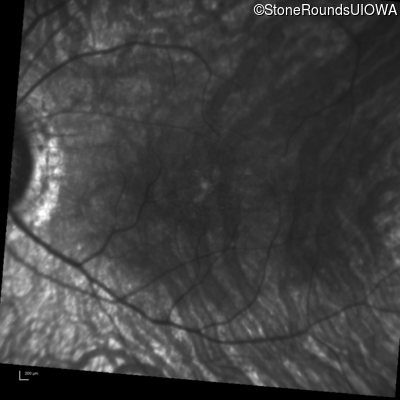

Infrared Fundus Photograph - Right - 20/80 sc

Exemplar